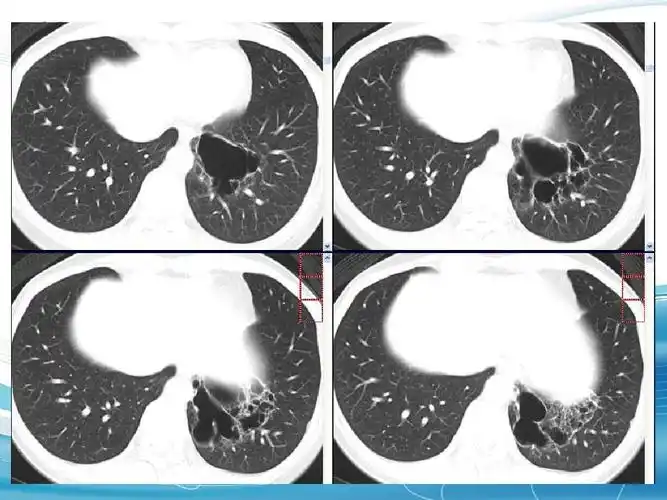

肺隔离症影像表现

本是同根生相煎何太急肺隔离症一例